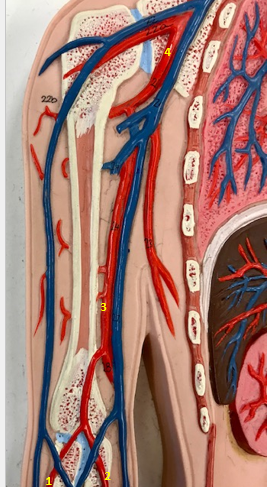

Tunica intima

Name the blue arrow

Lines lumen and release vasoactive chemicals

Function of tunica intima

Venous valves

Name the pink arrow

Prevent backflow of blood

Function of venous valves

Tunica media

Name green arrow

Vasoconstriction and vasodilation

Function of tunica media

Tunica externa

Name the purple arrow

Anchor and bind vessel

Function of tunica externa